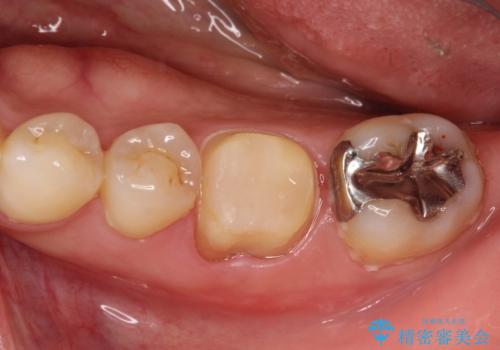

- 噛んだ時の痛みを主訴に当院受診されました。

根管治療を行なったのち、症状改善を認めオールセラミッククラウンにて修復治療を行なっております。

┌7は今回の治療後打診(-)、正常歯髄へ診断のもと経過観察を行なっております。